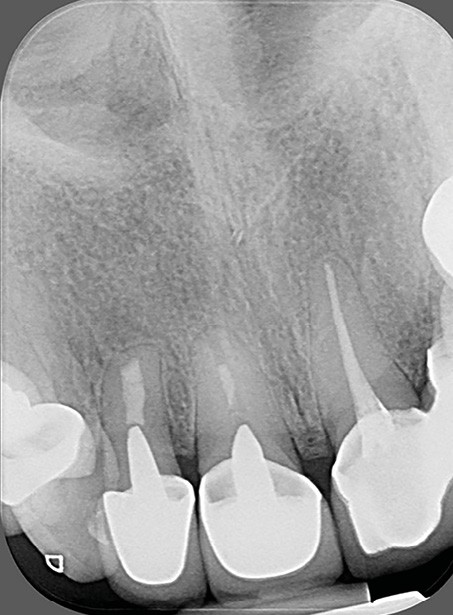

- un retraitement ne parviendrait pas à gérer une situation iatrogène : par exemple, une lésion accompagnée d’une importante extrusion de matériau d’obturation (fig. 3a-b).